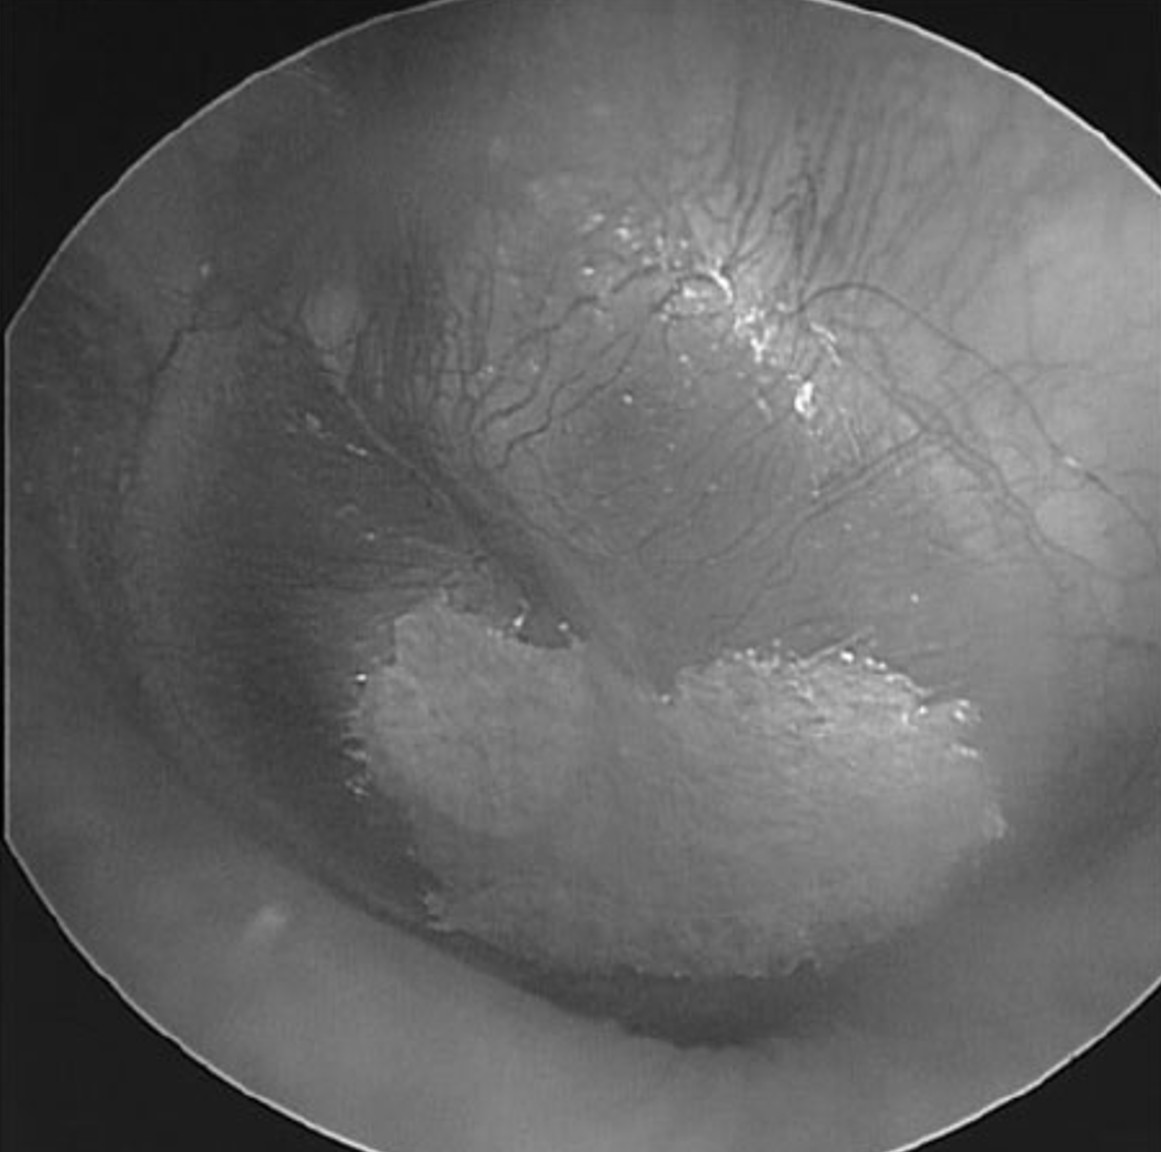

The images above show placement of paper patches on the tympanic membrane. The image on the left shows a single patch covering the inferior half of the eardrum, while the image on the right shows two patches covering the superior half. These images are from a 2014 article published by Dr. Michael Boedts, which describes the use of tympanic membrane paper patching to reduce symptoms of patulous Eustachian tube syndrome.